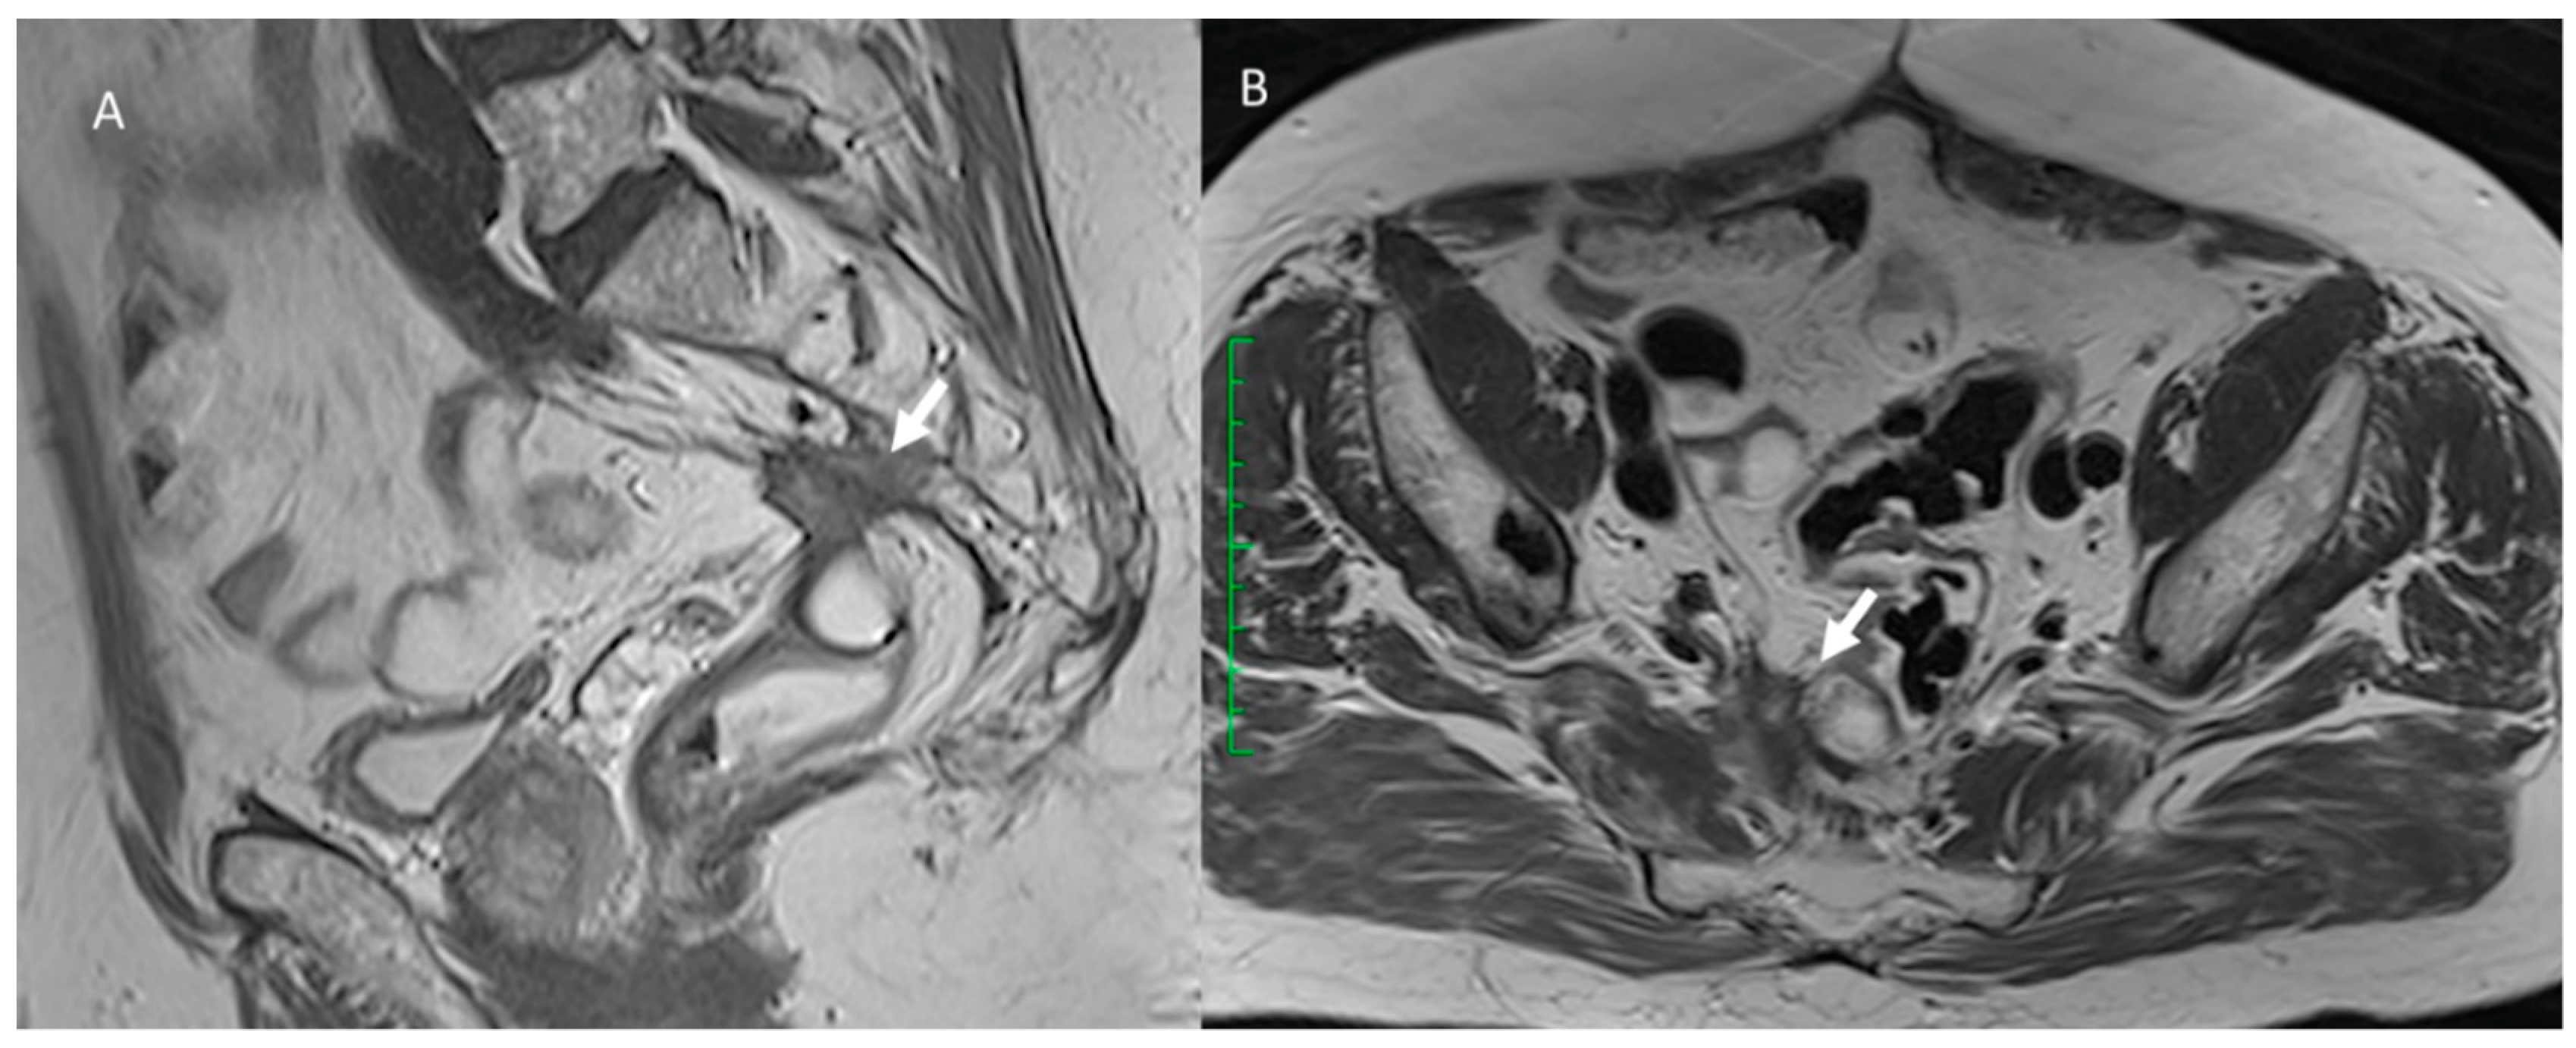

3.2. Fistula

3.3. Bleeding

3.4. Urological Injury

3.5. Wound Infections

3.6. Hernia

3.7. Local Recurrence